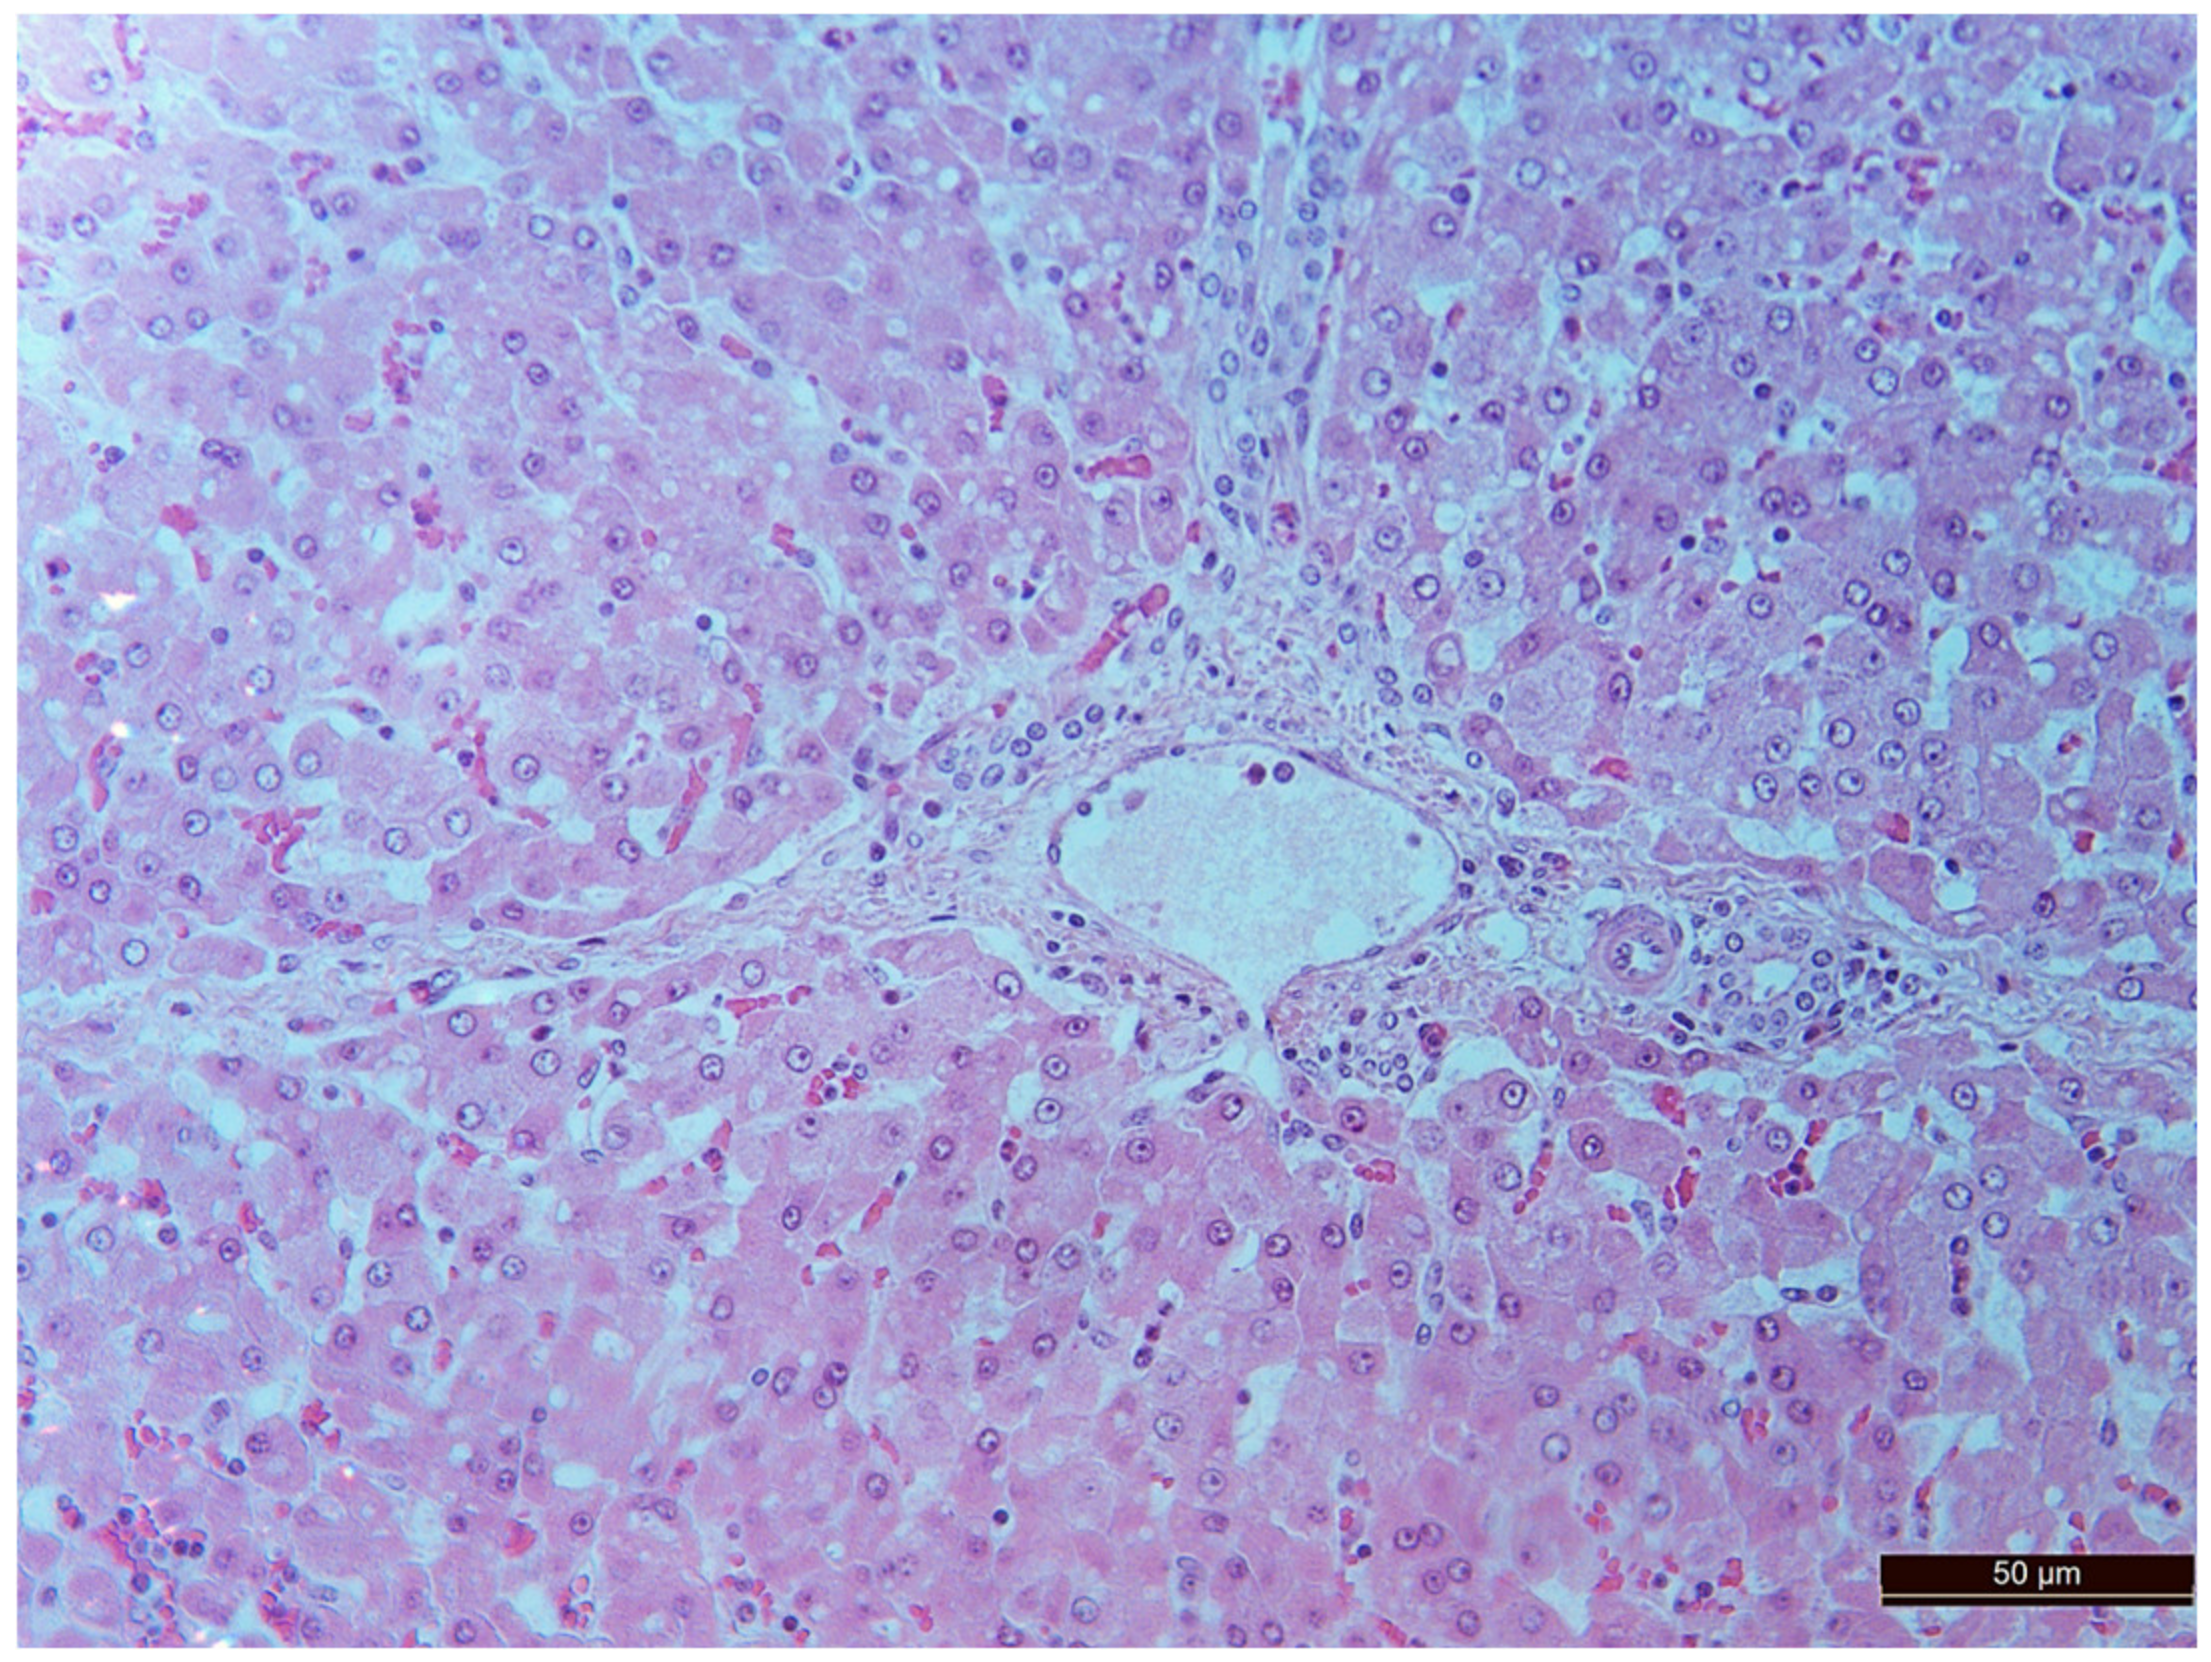

3.2. Pathology of the Liver